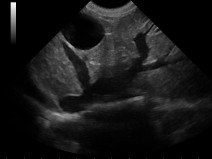

- décrire la présentation clinique des principaux cancers rencontrés dans l’espèce féline et les outils (biologiques, imagerie) indispensables de la démarche diagnostique ;